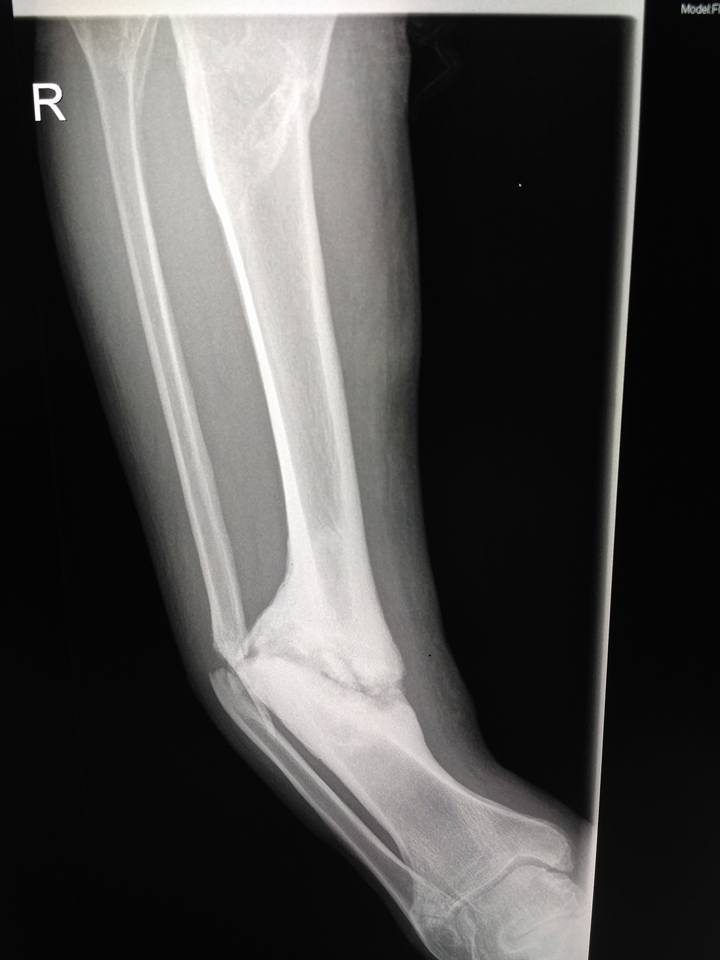

[Ortho] Псевдартроз tibia с варусной деформацией

Пациент мужчина 40 лет. Около 2-х лет назад травма. Лечили со слов

пациента гипсом, не было страховки, прописки и все было отягощено

хр.алкоголизмом.

Сейчас пациент встал так сказать на путь истинный, не пьет больше года,

выправил документы и хочет прямую ногу.

В области перелома в нижней трети подвижности практически нет, нога опорная.

Коллеги, какие мнения? Вопрос, стоит ли попытаться одномоментно

исправить ситуацию стержнем или растянуть сразу не удастся? Стоит ли

делать коррекцию в верхней трети?